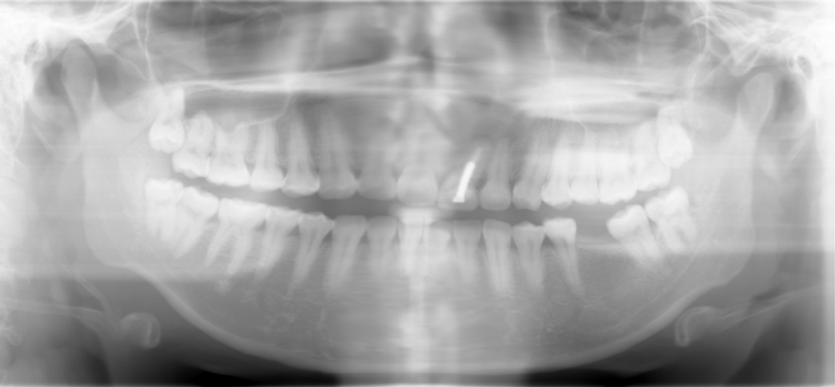

Comprehensive Treatment

23 year-old female, "I want braces"

Dental history: #9 fracture at age of 8; #9,10 crowns (joined) 2 years ago; #9 has chronic apical infection, #19 extracted due to caries at age of 15

#1,16,32 extracted before comprehensive exam, after pan taken

Problems and Treatment sequence

Caries control

Remove #9,10 crowns, #9 lingual margin subgingival; pulpal test: #8,10 necrosis. Remove #9 post, redo RCT, #8, 10 RCT, #8,10 in office internal bleaching; #9 cast post, ortho extrusion before #9,10 crowns

#18 mesiolingual tilt, #19 traditional implant and extract #17; once #19 implant is osteointegrated, it is to be used as an anchorage to upright #18, elastics between #15 buccal hook and 18 lingual button to correct linguoversion of #18

#14 supraeruption, mini-implants, orthodontic intrusion

Start tradtional orthodontic treatment